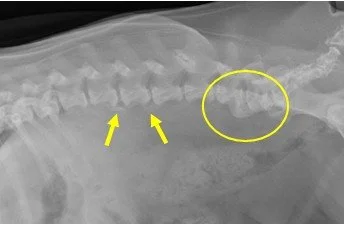

Llew was picked up by animal control off the streets of Hayward. He was unable to use his back legs. Otherwise he seemed in fairly good shape. He must not have been on the streets for long. It is suspected that he had a back problem (IVDD) that was never treated. He has responded well to anti-inflammatory and pain medications. He has gained some use of his back legs (he can stand and walk a few steps). He has been in physical therapy for a few months.

UPDATE: With diligent persistence from his foster home, Llew is walking again on his back legs. He is a little wobbly, but he is using his back legs all the time - no more dragging.

He needs a home with no stairs, and where someone is home most of the time. He would prefer a home with another friendly dog. Nobody’s Perfekt Dogs is willing to assist with his vet costs, if needed. Even though he has regained the ability to walk with his hind legs, the jury is still out on whether he has control of his bladder and bowels. He appears to pee when he goes outside, but he doesn't stop and pee. Similarly, he doesn't stop and poop - it just comes out when it is ready.